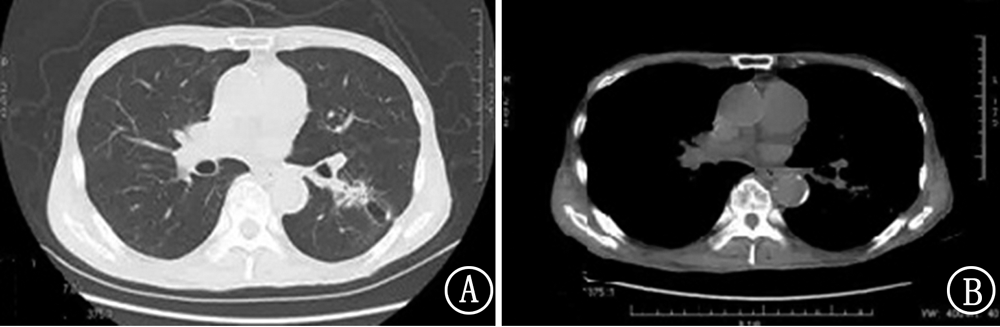

纳武单抗在肺鳞状细胞癌治疗中已广泛应用,但目前对药物引起的不良反应和处理了解有限。现报道1例纳武单抗治疗老年肺鳞状细胞癌的临床诊治经过,以此提高对该疾病治疗的相关认识。